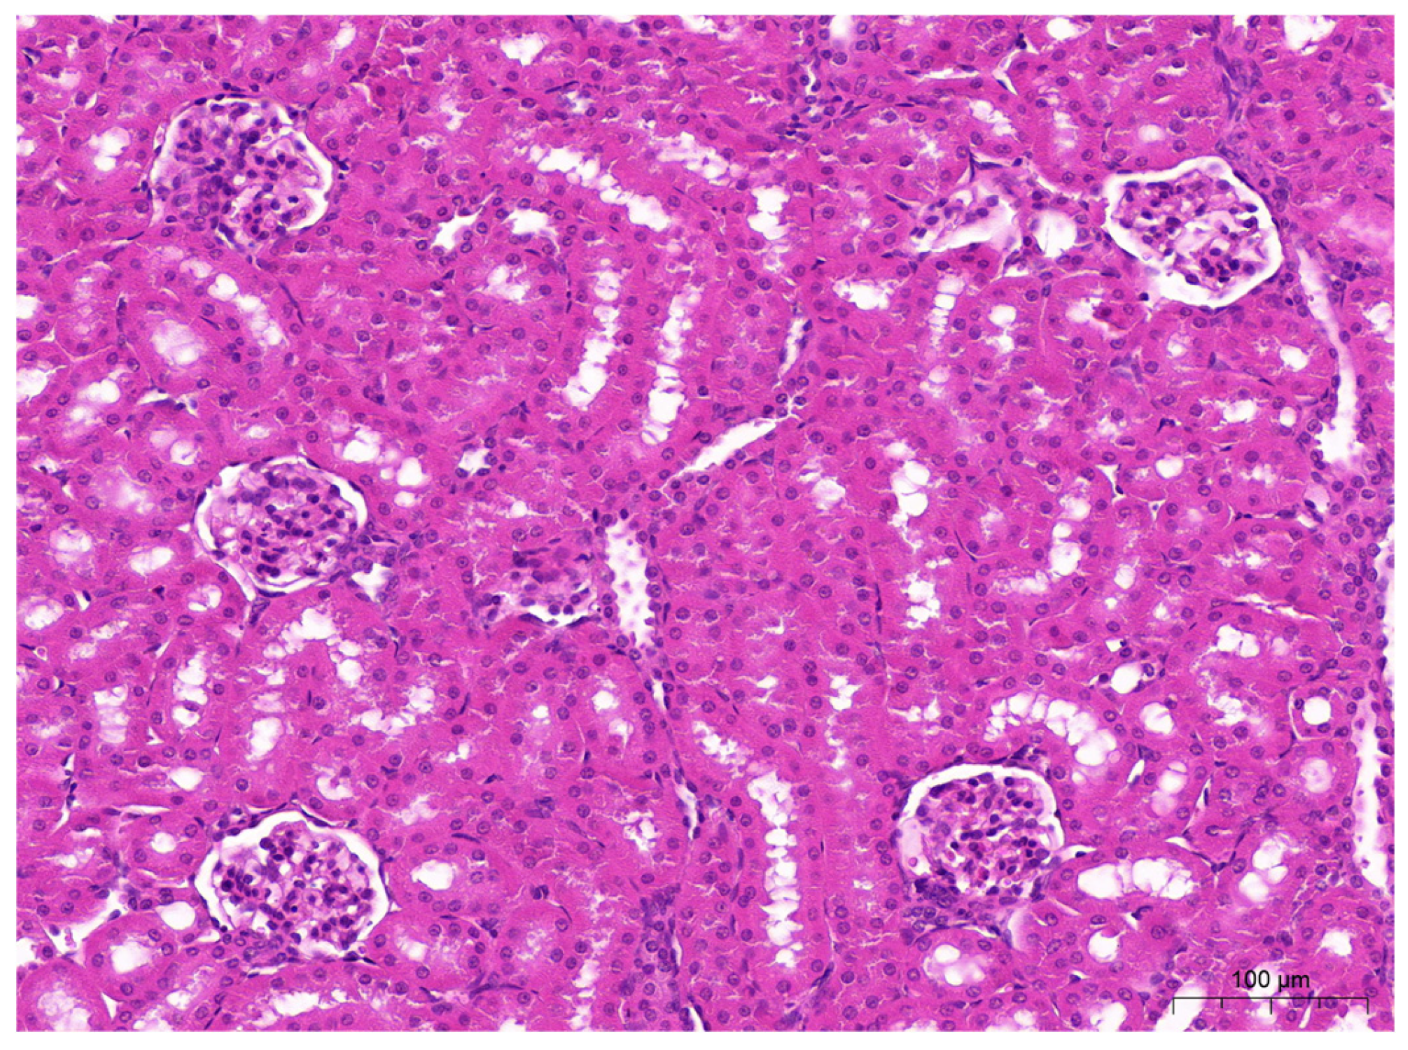

2.5. Histopathological Examinations of the Liver and Kidneys